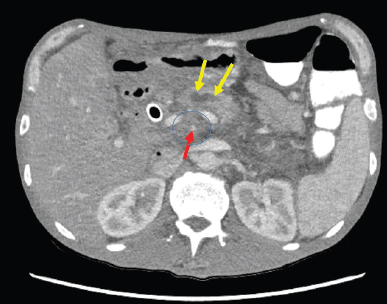

A CT scan of the abdomen reported a newly-found pancreatic mass in the pancreatic head/uncinated process (Figure 1), about 3.5 × 2.5 cm in size and encasing the superior mesenteric artery and occluding the superior mesenteric vein near the splenoportal confluence. Biliary ductal dilatation was also reported. The patient underwent endoscopic retrograde cholangiopancreatography (ERCP) and a metal stent was placed in the common bile duct. Post-ERCP, patient was discharged home to follow-up in the oncology clinic. The biopsy of the pancreatic mass reported pancreatic adenocarcinoma, the patient was found to have locally advanced disease with no distant metastases. CA19-9 was 142 U/mL (ref 0–35 U/mL).

Figure 1. CT Abdomen showed 3.5 x 2.5 cm primary tumour in pancreatic head/uncinate process mass with complete encasement of superior mesenteric artery (SMA)/superior mesenteric vein (SMV). No evidence of any regional lymphadenopathy or liver metastasis. The figure illustrates the approximate extent of pancreatic mass (circled), pancreatic duct dilatation (yellow arrow) and the narrow superior mesenteric artery (red arrow).